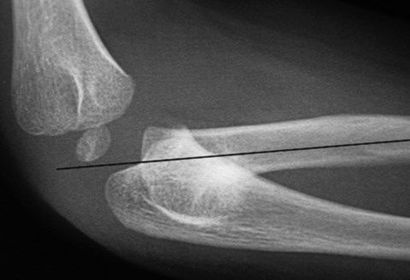

a. outer ridges of capitulum and trochlea b. trochlear notch c. trochlear sulcus

1. trochlear sulcus 2. outer ridges of capitulum and trochlea 3. trochlear notch

AP Lateral Elbow 60-75 kVp 40 SID 10x12 IR nongrid CR @ midelbow joint MUST SEE 3 concentric arcs, olecranon process